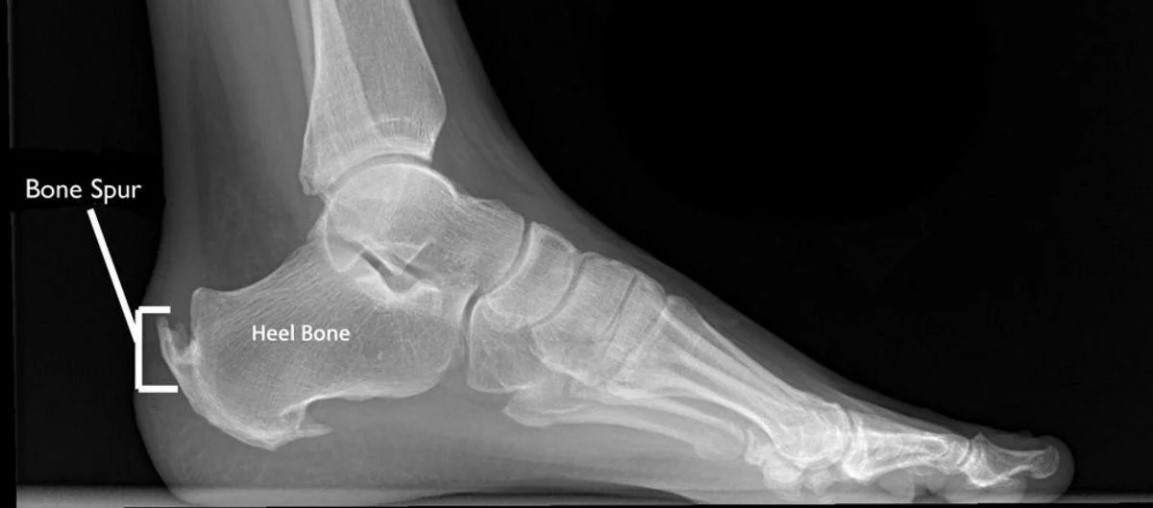

Remove Bone Spur Without Surgery . Taking apple cider vinegar each day is said. There are several popular natural remedies for removing bone spurs without the use of surgery. Tell your healthcare provider if you develop. Face the wall a few feet back with your left foot in front of your right foot. if you have bone spurs without symptoms, you don’t need treatment. wall calf stretch. understanding bone spurs and why they occur is essential to learning how to dissolve bone spurs naturally. some people with painful bone spurs due to osteoarthritis may benefit from surgery if other treatments don't work. most patients with mild or moderate nerve compression and irritation from bone spurs can manage their. Lean toward the wall, allowing your left knee to.